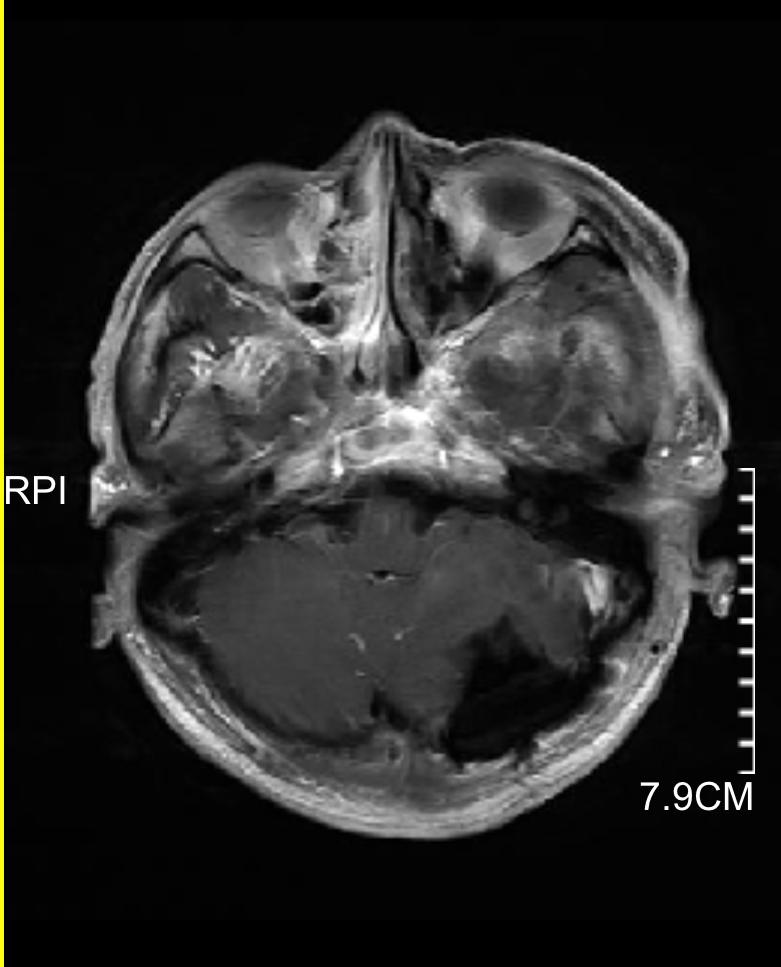

下图的病例是一个以头痛、行走不稳为主要表现,查头颅磁共振发现颅内三个大的转移灶,同时肺部发现巨大肿瘤,脑内病灶给予全部切除,术后根据基因检测结果进行化疗及靶向、免疫治疗。

小脑巨大转移瘤

顶部稍小转移瘤

颞部巨大转移瘤

小脑转移瘤已切除

顶部转移瘤已切除

颞部转移瘤已切除